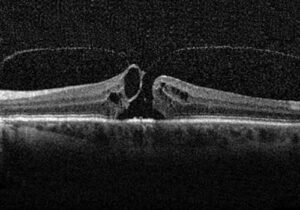

Foro maculare

Il foro maculare è una patologia caratterizzata dalla formazione di una sol...

Dettaglio foro maculare